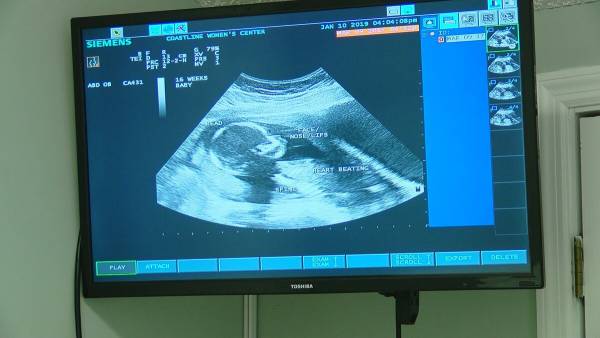

图源:得克萨斯先驱报